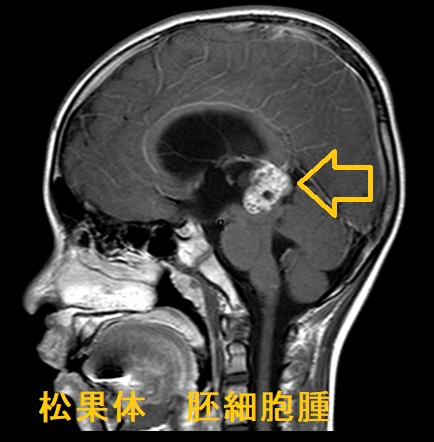

松果体部腫瘍の症状は

- 中脳水道狭窄による水頭症・頭蓋内圧亢進症状

- 視蓋前域の圧迫;眼球運動障害・上方注視麻痺、眼瞼下垂、瞳孔の対光反射・調節反射の消失(Parinaud症候群)

- 特に男児で視床下部の圧迫により思春期早発症

β-ヒト絨毛性ゴナドトロピン(hCG)、はα-フェトプロテイン(AFP)が上昇松果体腫・松果体芽腫は上昇しない

治療は外科的切除、術後放射線治療・抗がん剤治療